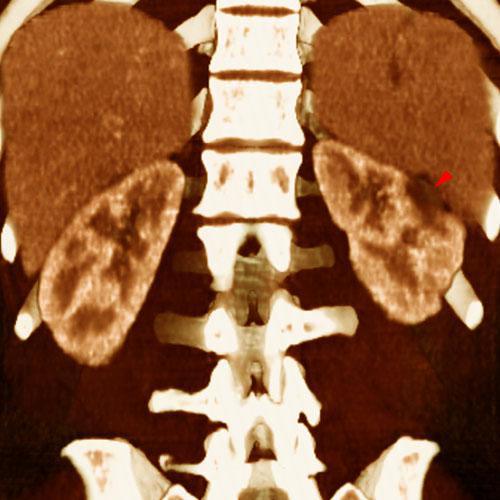

Infartos renales múltiples

VR seccional. Visión coronal anterior. TC contrastado en fase venosa. Lesión hipodensa y periférica (punta de flecha) en un paciente con neoplasia broncopulmonar